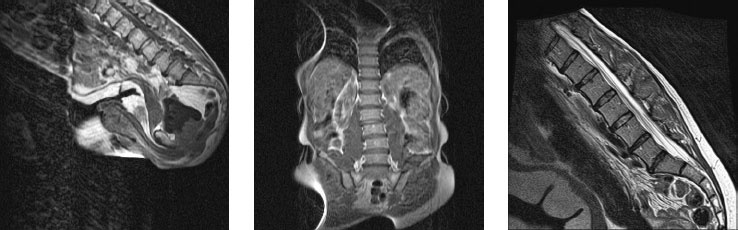

Рисунок 24. Несмотря на разные школы, разные десятилетия, разные континенты, разный пол и разный по продолжительности опыт занятий йогой, здесь мы не видим значительных различий в положении поясничных позвонков.